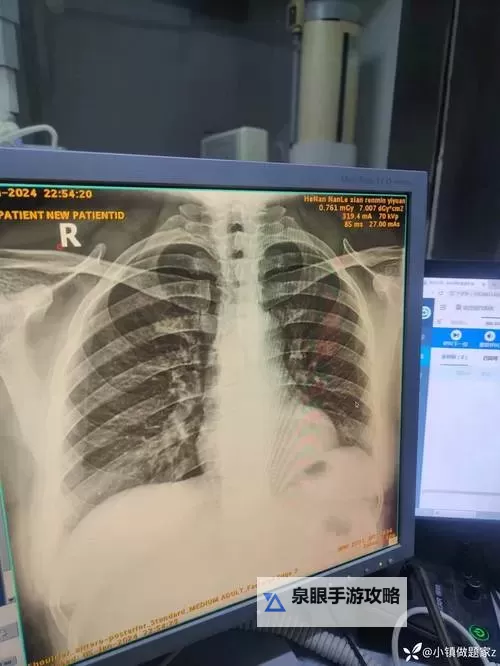

近年来,随着数字化技术的高速发展,胸部X光片(胸片)的获取、存储和分析实现了革命性的升级。2025年,数字化胸片技术已成为行业的主流,大大提高了诊断的效率与准确性。相比传统胶片,数字胸片具有体积小、便于存储和传输、图像清晰度高等优势,极大地方便了临床医生的操作与判断。此外,云存储和远程诊断技术的应用,使跨地区、跨医院的医学合作变得更加便捷,为偏远地区的患者带来了福音。

在最新的动态中,人工智能(AI)和深度学习技术的引入成为焦点。2025年的胸片分析,依托先进的AI算法,不仅能快速检测肺结节、结核、肺炎等常见疾病,还能辅助医生对异常变化进行精准判断。这些算法通过大量的学习与训练,已能在几秒钟内完成对异常影像的筛查,大幅度缩短了诊断时间,提高了检测的敏感性和特异性。据统计,AI辅助诊断的准确率已接近甚至超过专家水平,成为临床不可或缺的“助手”。